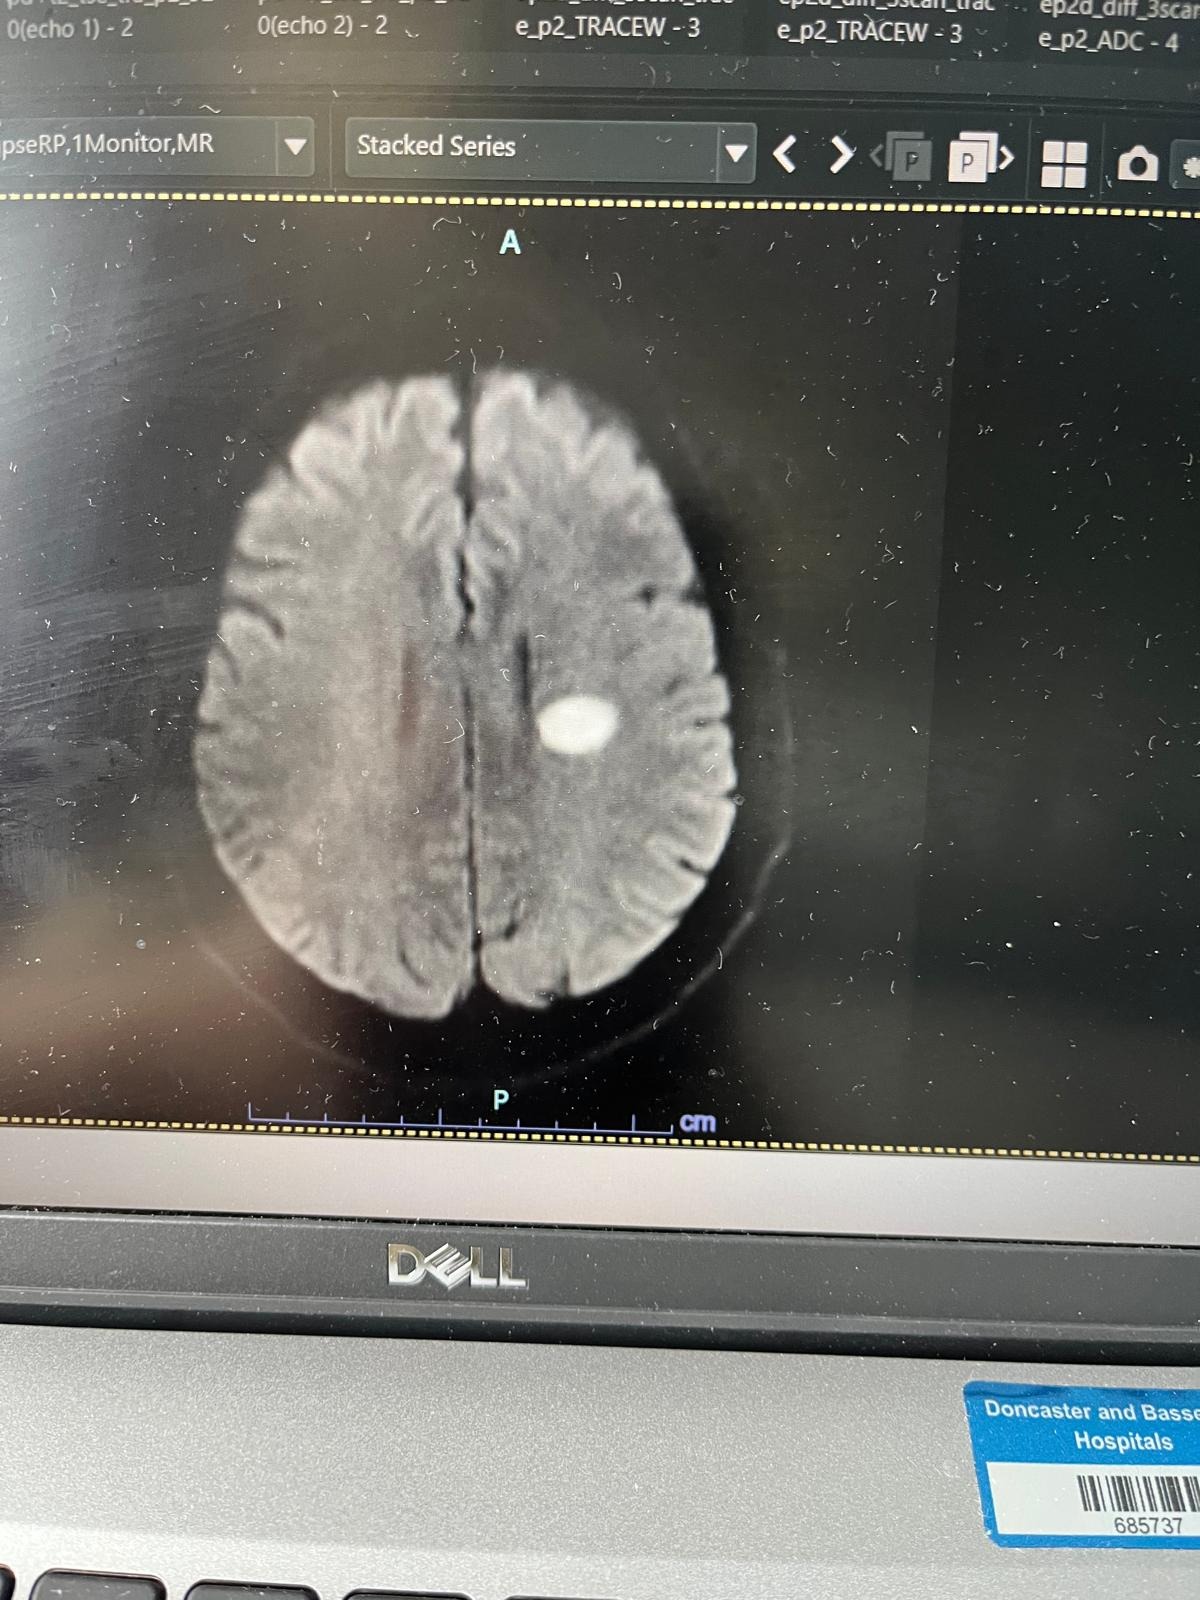

Out of the blue, Jeff was rushed by blue lights to Doncaster Royal Infirmary’s Stroke Unit, where he spent his first week undergoing extensive tests. He was diagnosed with a lacunar stroke, caused by a blood clot deep in the centre of his brain. There were no warning signs and no underlying conditions, just terrible luck.